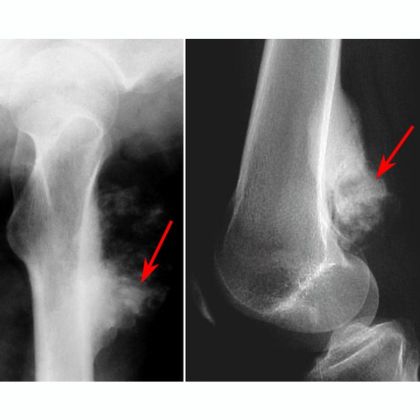

B. Badania obrazowe

- Rentgen: Rentgenografia jest często wykorzystywana jako pierwsze badanie obrazowe w diagnostyce nowotworów kości. Pozwala ona na uzyskanie obrazu struktury kostnej i potencjalnych zmian nowotworowych.

- Tomografia komputerowa (TK): TK pozwala na uzyskanie bardziej szczegółowych obrazów struktury kości i tkanek miękkich, co może pomóc w określeniu rozległości guza oraz ewentualnego zaangażowania tkanek otaczających.

- Rezonans magnetyczny (MRI): MRI jest często stosowana w diagnostyce nowotworów kości, ponieważ umożliwia uzyskanie bardziej szczegółowego obrazu tkanek miękkich i zapewnia informacje o ewentualnym nacieku guza na otaczające struktury.